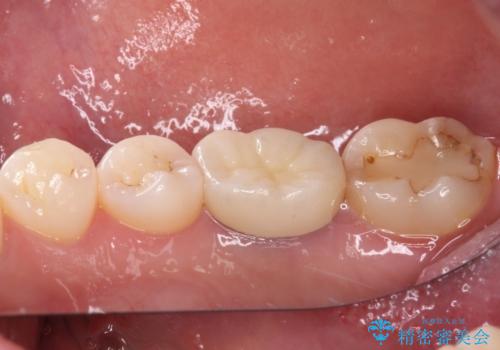

口腔内から、土台も含め銀歯がなくなったことでメタルフリーとなりました。